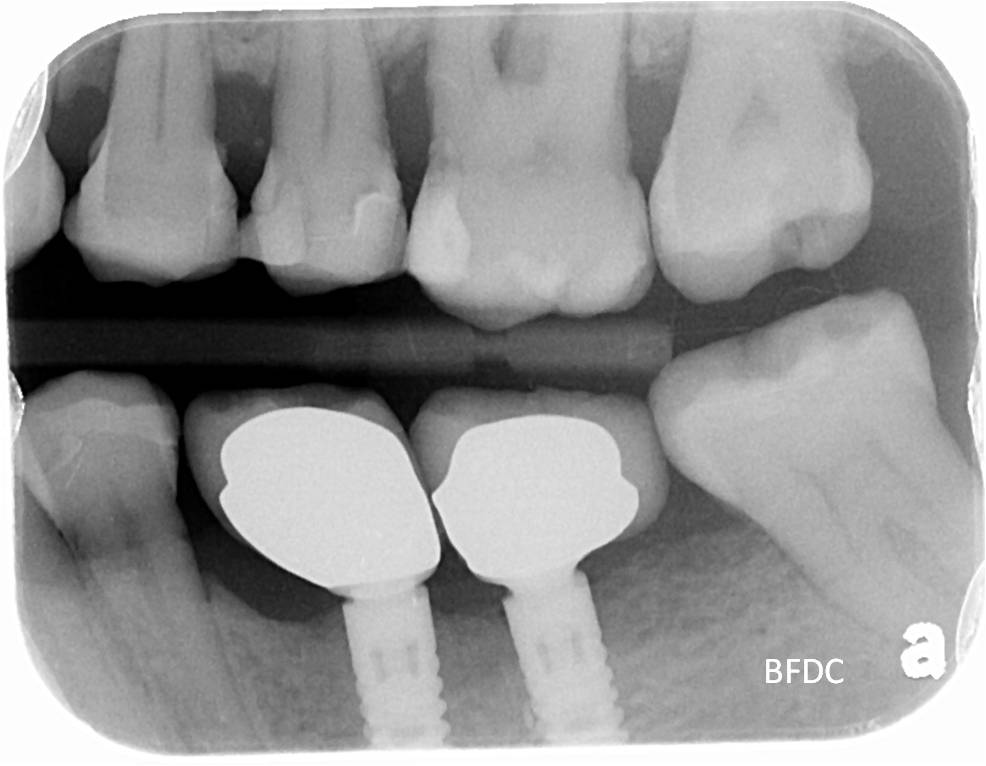

治療前根尖片評估